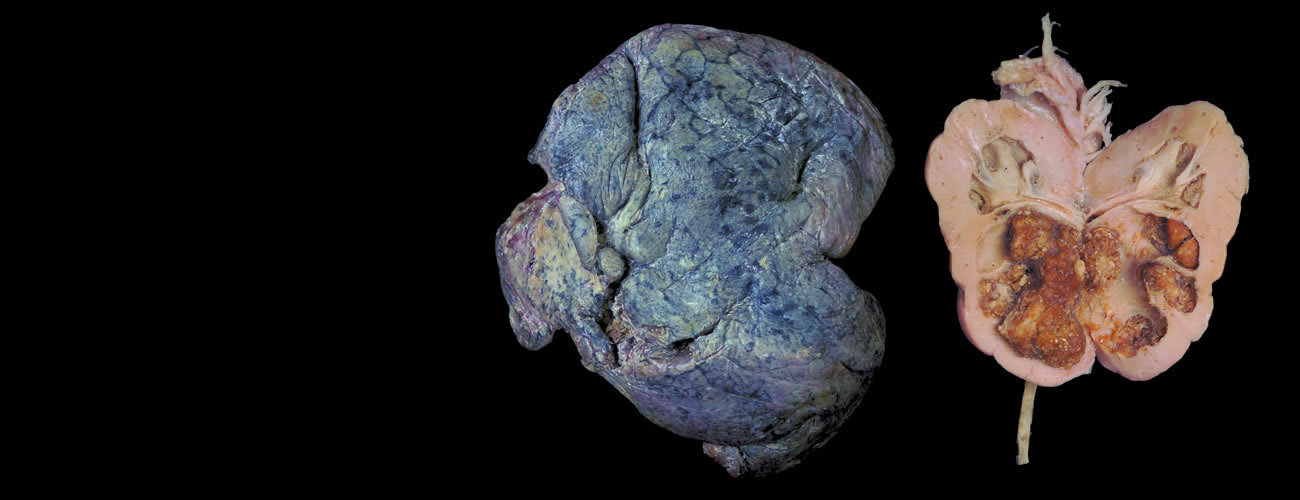

william威廉英国医学标本馆是融医学多学科资源于一体的现代化医学标本博物馆,目前主要由标本馆展区、医学模拟中心、志愿遗体捐献登记接受站与志愿者服务基地三大模块组成,占地面积5000多平方米,馆内收藏的医学标本数量丰富、种类齐全,是william威廉英国医学教育发展近150年的历史缩影与历史见证。